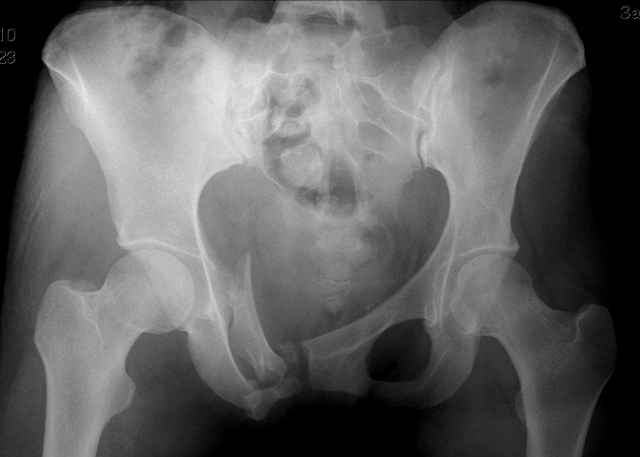

Уважаемые коллеги!

Серия до- и послеоперационных снимков этой пациентки. Хотя бы post factum обсудить. Не знаю, что можно сделать с задними отделами стержневым аппаратом, но три крепких парня открытым путем с помощью "волшебных" слов еле-еле смогли отрепонировать - сзади все было очень ригидно!

Здравствуйте, Евгений! У меня видна только дооперационная проекция inlet.

я бы остановился на передней раме, операция - 30 мин, в таком варианте вроде бы репозиция - ничего, но когда давать нагрузку, ведь в лонном сочленении тоже есть подвижность? а если не давать - зачем операция?